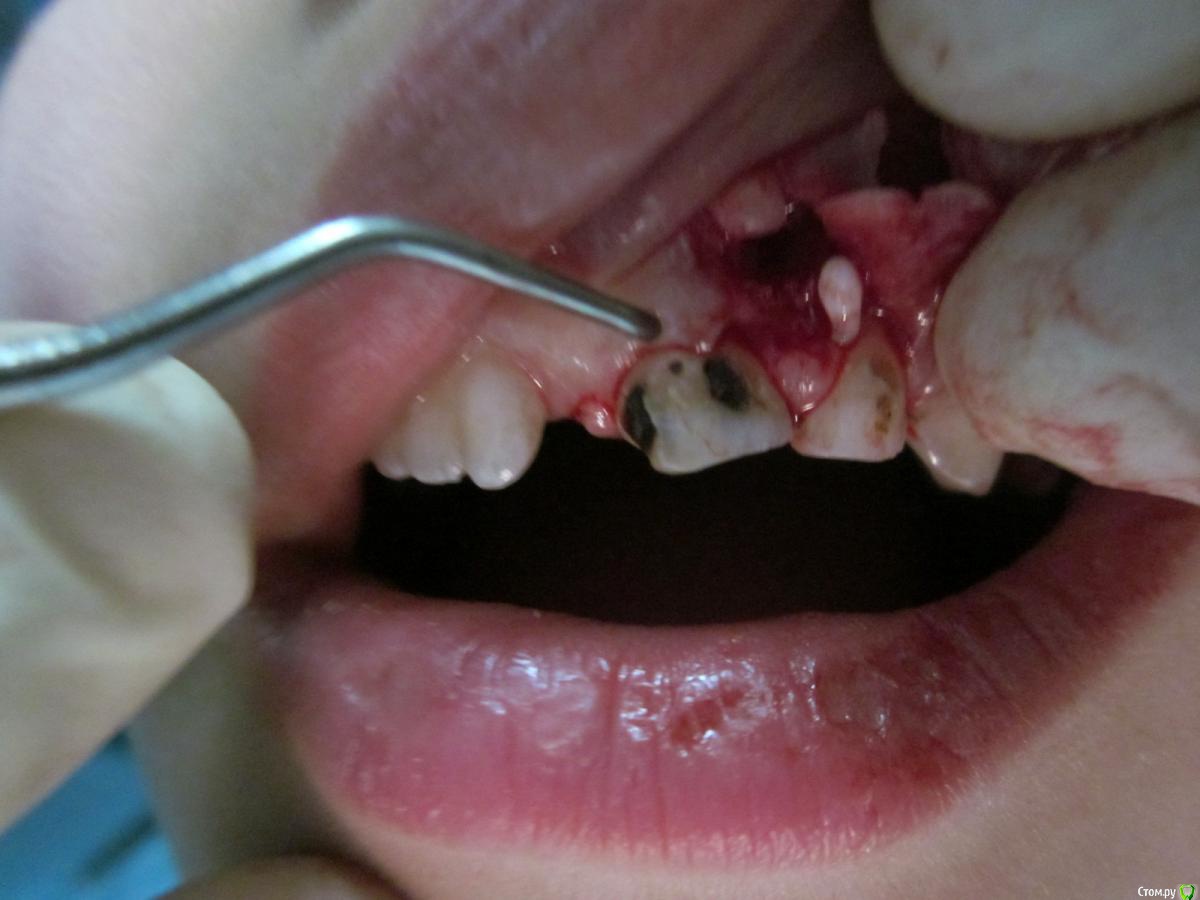

По данному случаю: пациент 6-7 лет, 21 не растёт, все динамят (ортодонты и терапевты), дошли до хирурга: на снимок прицельный, что то не то, на КТ охарактеризовал как одонтому. Операция под

анестезией Ультракаин дс, кортикальную пластинку трепанировал «расковырял» эскаватором, убрал конгломерат тведых тканей, саму оболочку, удалил 61. Биологический материал в пробирку с физ

раствором, направление на исследование в гистологию и ГОУ самим.